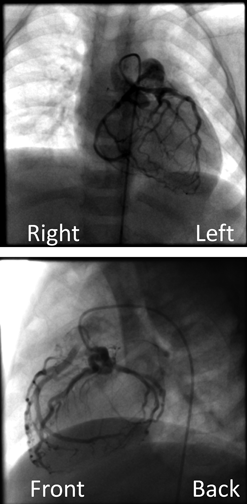

体重増加不良の精査に行った心臓超音波検査が診断につながった右冠動脈肺動脈起始Anomalous Origin of the Right Coronary Artery from the Pulmonary Artery Diagnosed by Echocardiography Performed for Close Examination of Poor Weight Gain